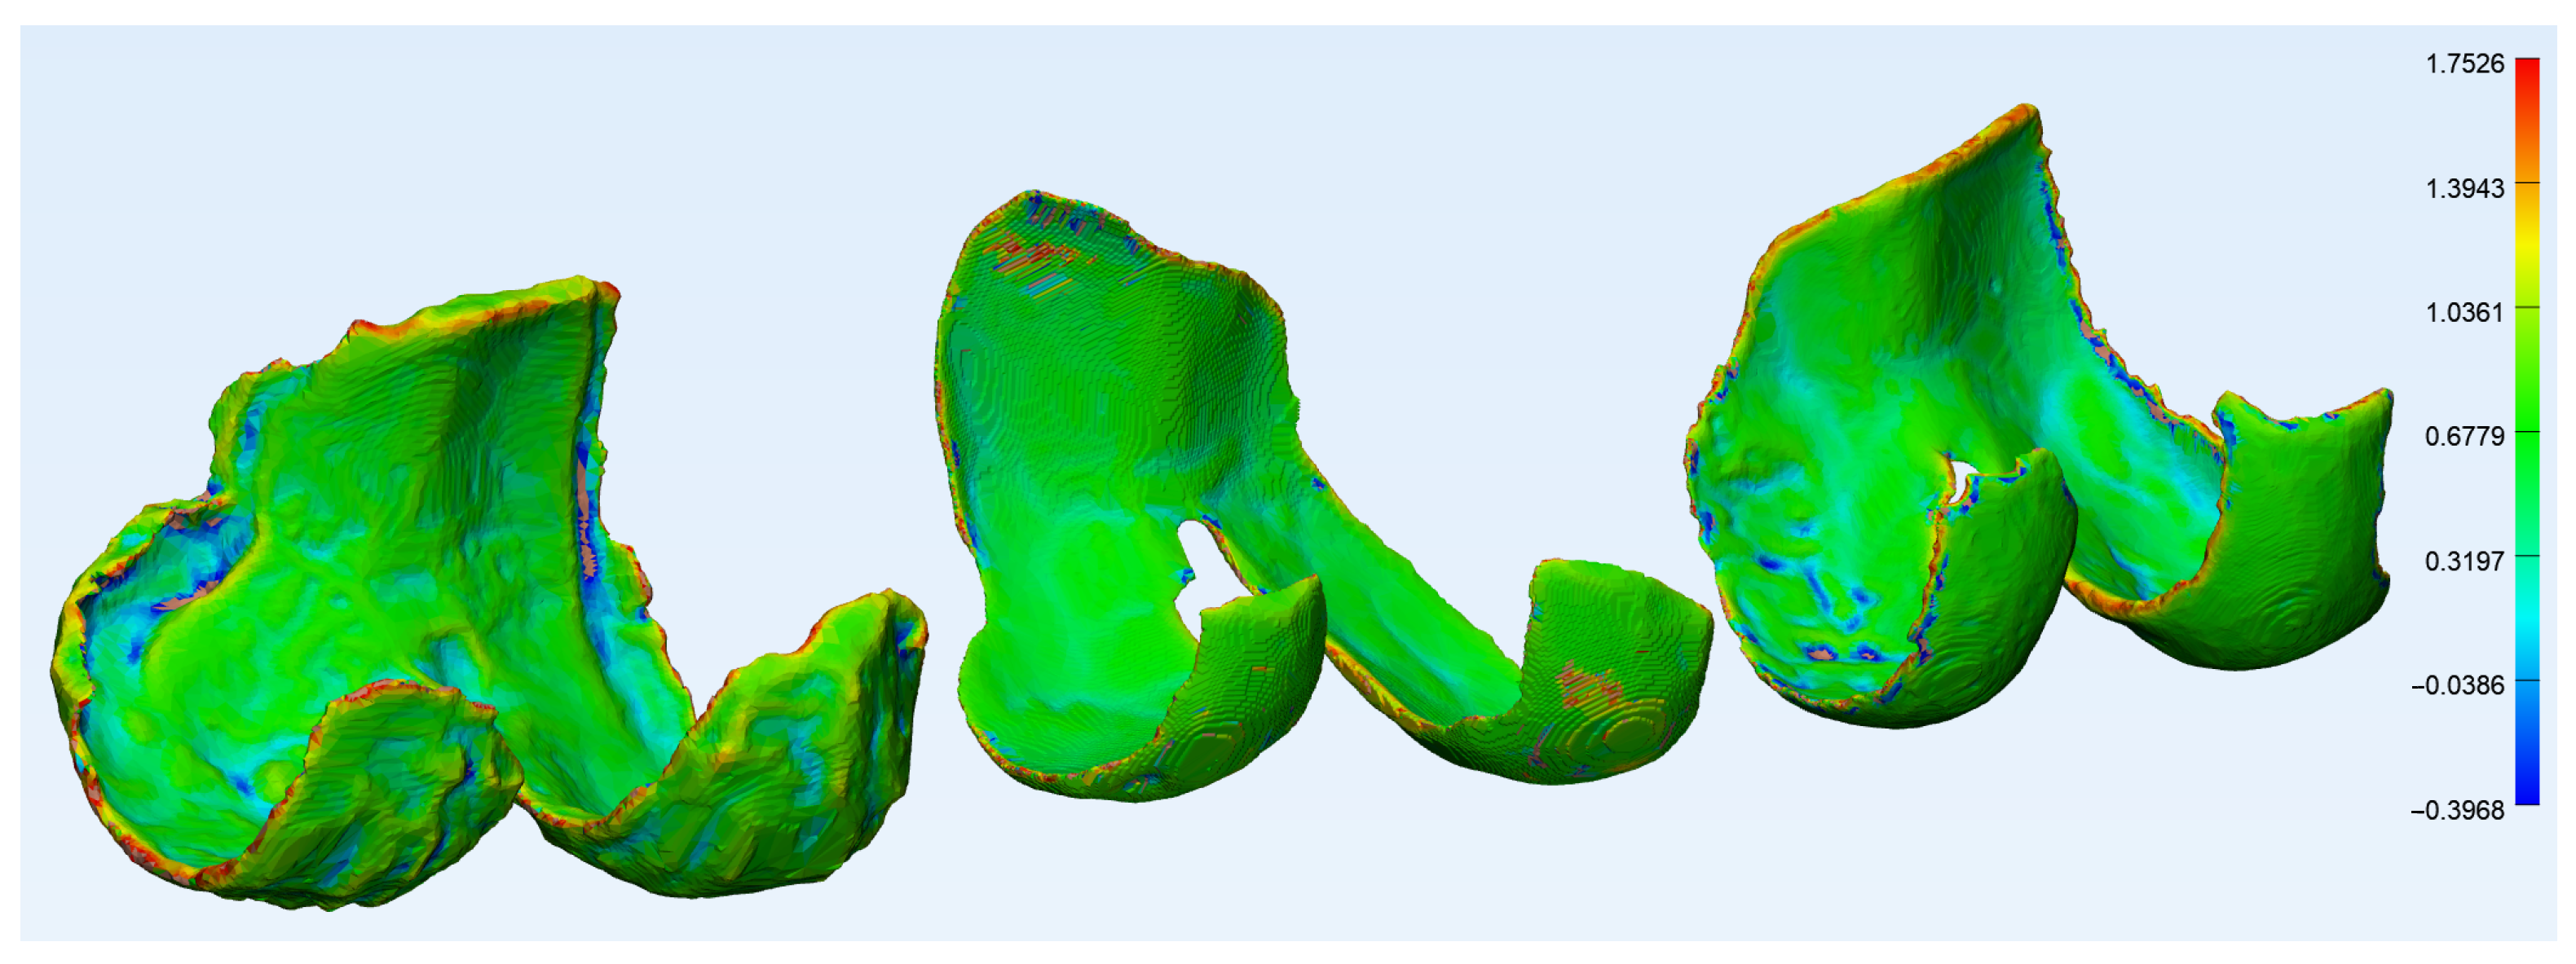

2.2.2. Wall Thickness and Curvature Analysis

3.2. Wall Thickness and Curvature Analyses